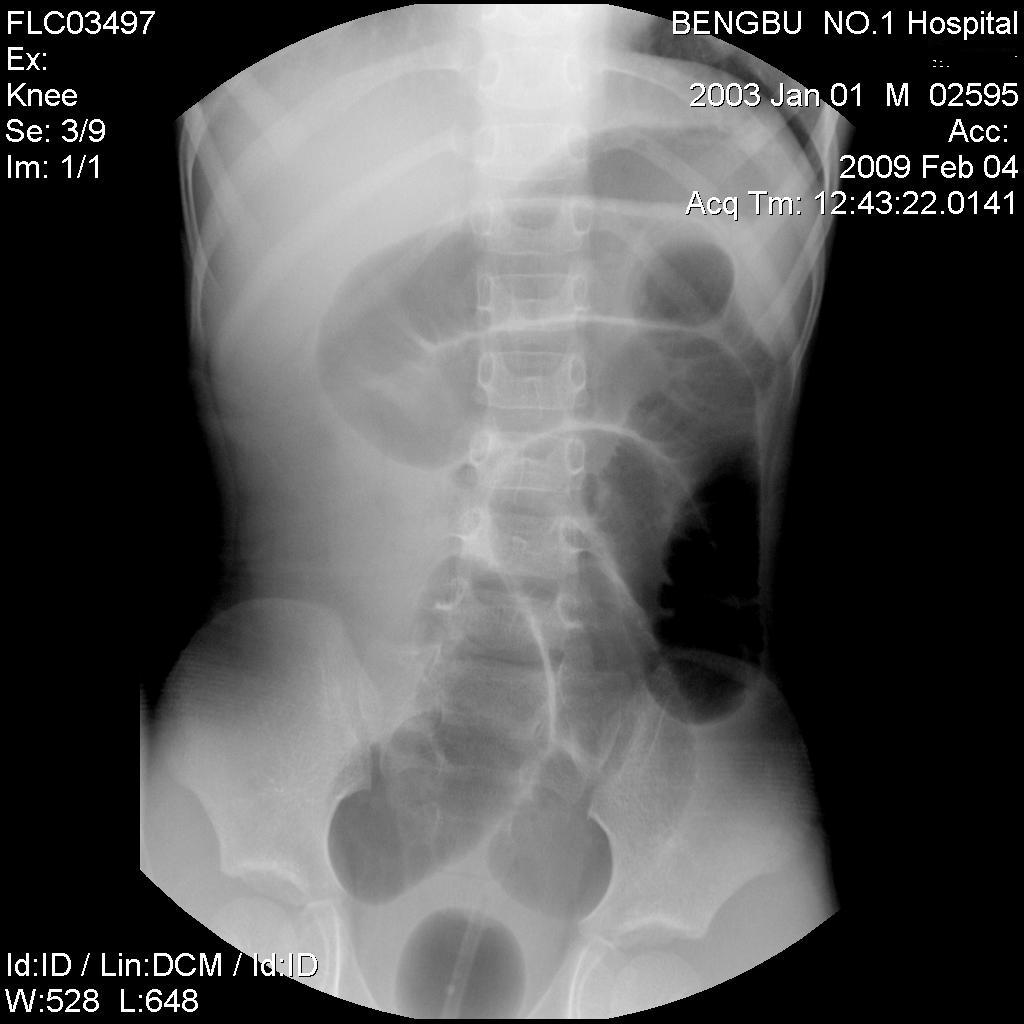

以下是引用杀毒软件在2009-2-5 14:51:00的发言:[br]提示肠梗阻----原因待查----大跨度肠绊---绞窄性可能性小---首选考虑---肠套叠或功能 性肠梗阻可能

以下是引用余辉在2009-2-5 8:52:00的发言:[br]考虑绞窄性肠梗阻,建议行钡剂灌肠检查

以下是引用随光逐影在2009-2-5 1:00:00的发言:[br]考虑肠套叠;建议行钡剂灌肠检查。